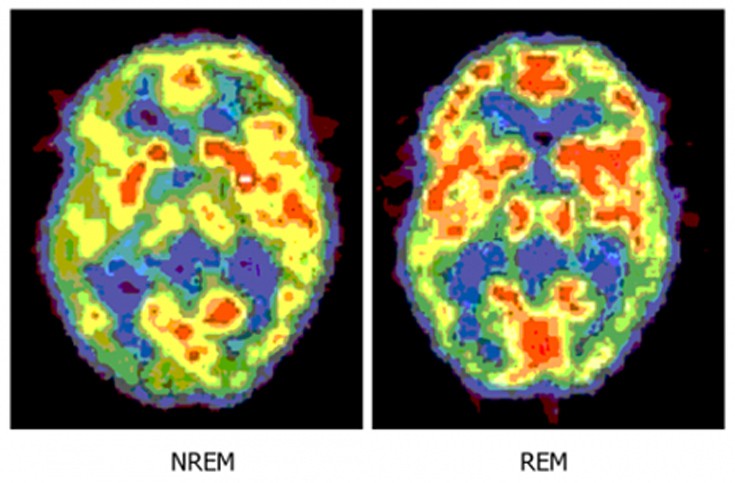

4. Ο εγκέφαλος είναι πιο «ενεργός» κατά τη διάρκεια του ύπνου

Η νυκτερινή ώρα είναι η κατάλληλη στιγμή για τον εγκέφαλό μας να επεξεργαστεί το σύνολο των δραστηριοτήτων που συνέβησαν κατά τη διάρκεια της ημέρας.

Γι’ αυτό και οι επιστήμονες εικάζουν ότι αυτός είναι ο λόγος που ονειρευόμαστε. Ορισμένοι πιστεύουν ότι είναι ένας τρόπος για να επεξεργάζεται τα πολύπλοκα συναισθήματα και τις αλληλεπιδράσεις της καθημερινής μας ζωής ενώ άλλοι πιστεύουν ότι είναι απλά ένας τρόπος για να μηδενίζονται οι πληροφορίες, όπως κάνει ένας υπολογιστής.